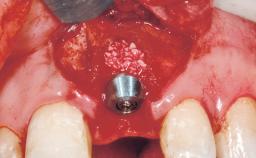

A 39-year-old male patient presented with a chief complaint of discomfort and gingival discoloration around his maxillary left central incisor. He was in good general health and was a non-smoker. His past dental history was significant because of the traumatic fracture of tooth 21 in a sporting accident at age 13. Initial dental treatment included endodontic therapy and a full-coverage restoration. The patient became symptomatic 5 years later, when structural failure of the tooth resulted in the dislodgment of the crown. Endodontic retreatment, apical surgery, and post-and-core restoration were performed.

| Placement Protocol | Early or late implant placement |

| Bone Volume | Deficient horizontally, requiring prior grafting |

| Soft Tissue Grafting | Simultaneous |